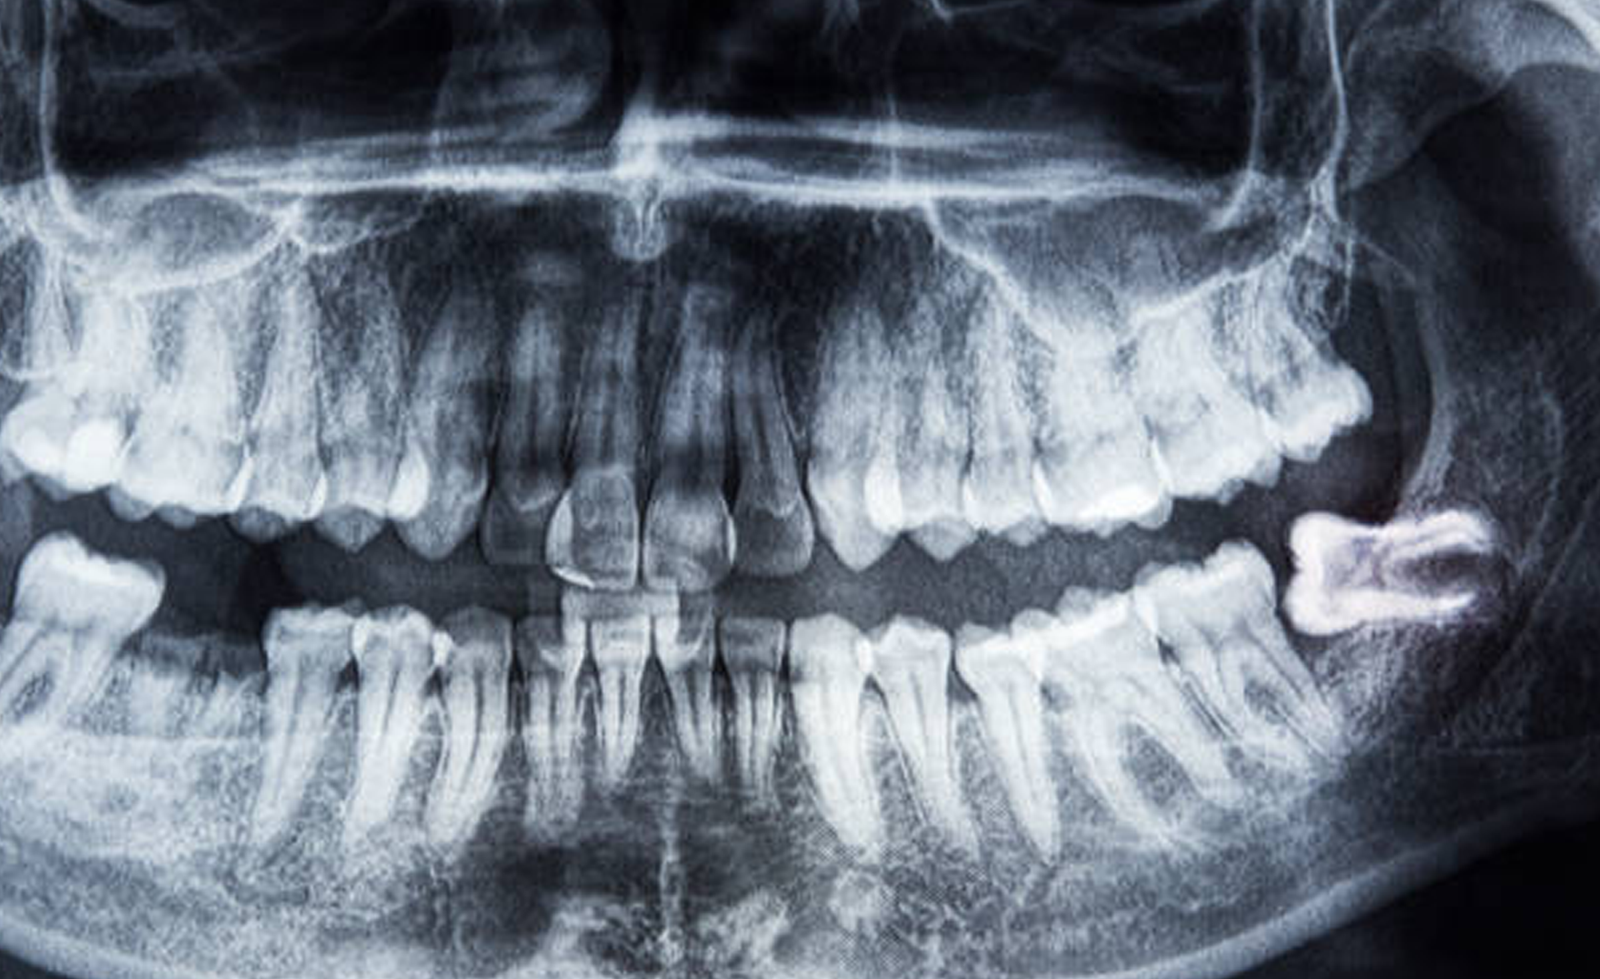

Molares (Muelas del Juicio)

Las muelas del juicio son los últimos molares y, a menudo, no tienen espacio suficiente para erupcionar, lo que puede causar problemas como infecciones, caries o apiñamiento dental. La extracción de las muelas del juicio es necesaria cuando están impactadas o pueden generar molestias.